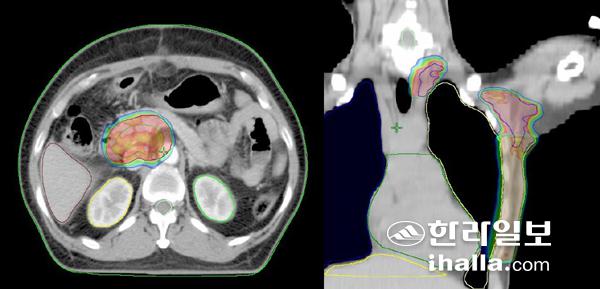

특수 치료를 통해 암 부위에만 집중적으로 처방된 방사선량을 전달한다. (왼쪽 담낭암, 오른쪽 유방암)

특수치료는 방사선을 전달하는 방법에 따라 세기 조절 방사선치료(IMRT; Intensity-modulated Radiation Therapy)와 입체 세기 조절 회전 치료 (VMAT; Volumetric Modulated Arc Therapy)로 나눠 볼 수 있다. 특수치료는 선형가속기 내부에 부착된 다엽콜리메이터(MLC: Multileaf Collimator)라는 텅스텐 재질로 구성된 구조의 발달로 빠른 속도로 방사선치료에 사용되기 시작했다. 방사선은 투과력이 큰 특성이 있지만 방사선이 진행되는 방향에 방사선 세기를 감쇄시킬 수 있는 특정 물질을 위치시키면 방사선 세기를 조절할 수 있다. 다엽콜리메이터는 방사선 치료기 내부에 부착해 방사선이 전달되는 동안 연속적으로 움직임으로써 방사선 세기를 필요에 따라 조절하는 역할을 하기 때문에 환자에게는 효율적으로 암 조직에 집중적으로 처방된 방사선량을 전달할 수 있다.

다음 단계에서는 방사선 치료계획을 시행하게 되는데 이 과정은 동일한 종류·부위의 암이라고 할지라도 환자에 따라 체형 및 내부 장기 구조가 다르기 때문에 앞서 찍은 CT 영상을 이용해 치료 방법을 계획하는 과정이다. 이때 방사선종양학과 전문의와 의학 물리학자 그리고 도시메트리스트가 협력해 CT 영상에서 암 조직과 정상조직을 정의하고 환자를 중심으로 방사선이 들어갈 방향과 사용할 방사선의 종류, 에너지, 방사선 세기 조절을 위한 다엽콜리메이터 움직임을 설정하는 등 환자 맞춤형 치료계획을 세우게 되는 것이다.